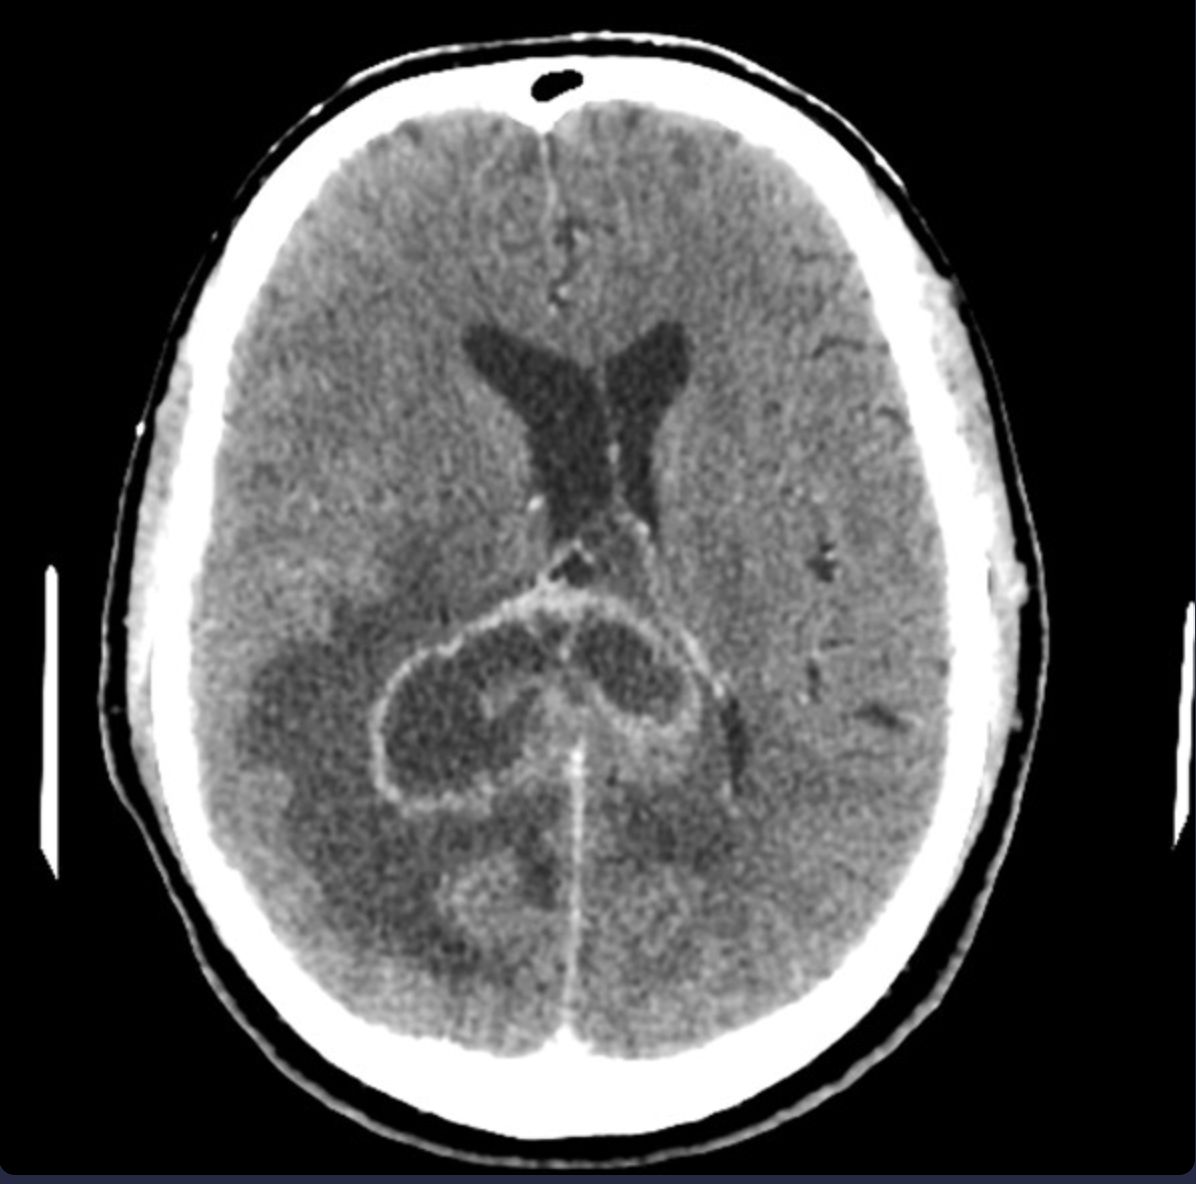

Brain tumor presenting with

- a short history of progressive neurological deficits and features of raised intracranial pressure.

- CT findings: irregular ring enhancement with central necrosis and significant mass effect.

- Occupational exposure to synthetic rubber manufacturing is a risk factor

A

Glioblastoma